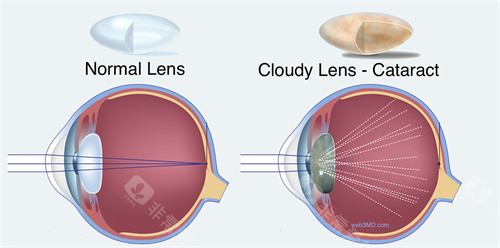

南京医科大学眼科医院提供了丰富多样的医疗服务。它涵盖了常见的眼科疾病治疗,如近视、远视、散光等屈光不正问题,能够为患者提供验光配镜以及各类矫正方案。对于白内障、青光眼等眼科疑难病症,也有相应的诊断和治疗手段。此外,医院还开展了眼部整形美容、小儿眼科等特色服务,满足了不同患者的需求。无论是日常的视力检查,还是复杂的眼部手术,患者都能在该医院找到合适的解决方案。

为了更好地进行眼科诊断和治疗,南京医科大学眼科医院配备了较为齐全的设备。在检查方面,有眼底照相机可以清晰拍摄眼底图像,帮助医生发现眼底病变;验光设备能够比较准测量患者的视力情况。在治疗设备上,有用于白内障手术的超声乳化仪等。这些设备为医生的诊断和治疗提供了有力的支持,有助于提高诊断的比较准性和治疗的结果。